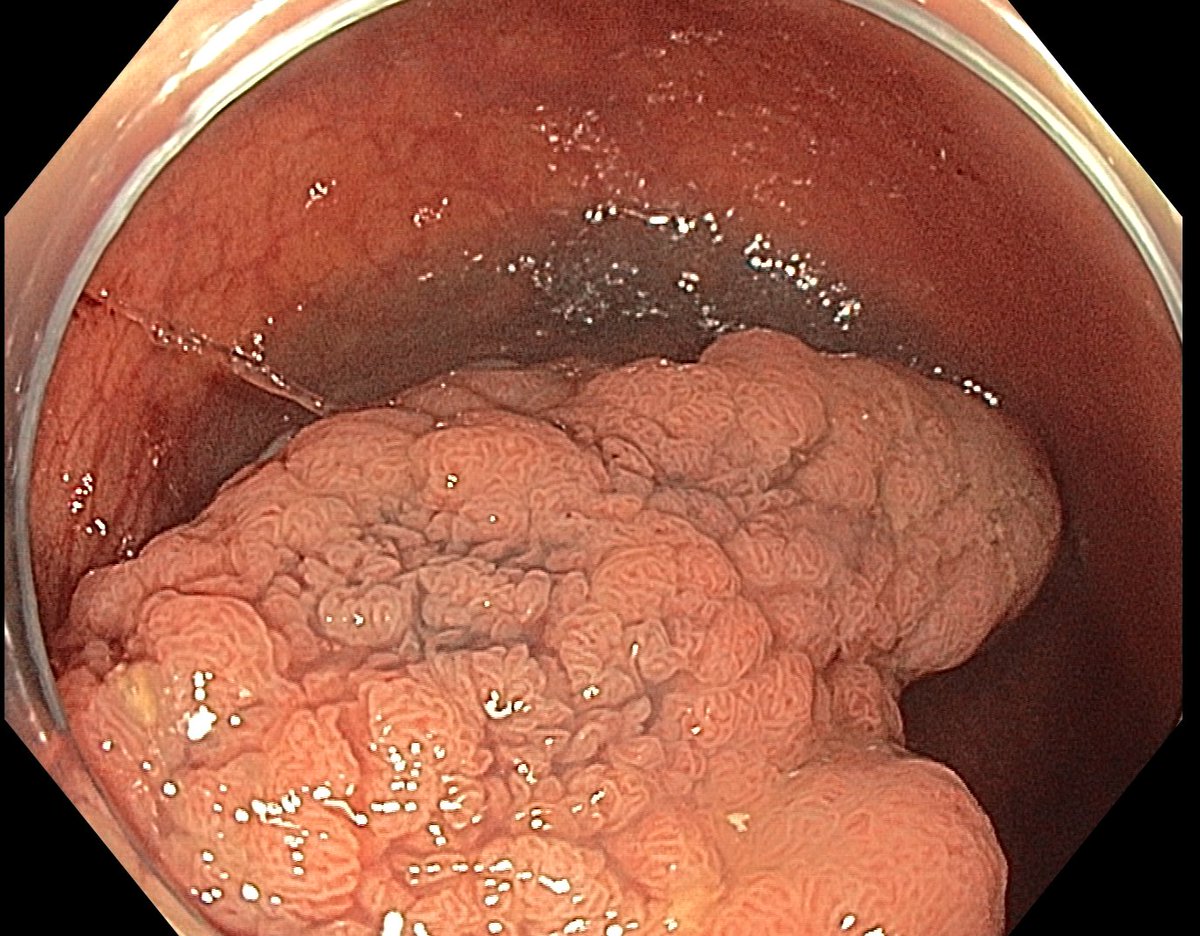

This lesion was diagnosed in the distal sigmoid colon? What do you do next?